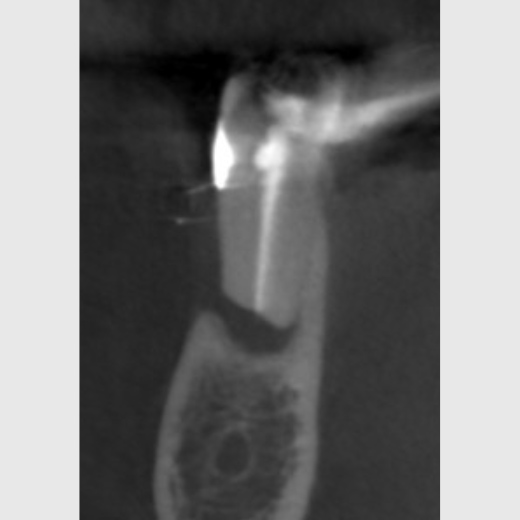

Perforationen bei einer Wurzelkanalbehandlung: Ist der Zahn noch zu retten?

Die Wurzelkanalbehandlung ist eine Therapiemöglichkeit, die höchstes Feingefühl erfordert und nicht immer läuft alles reibungslos. So kann es zu sogenannten iatrogenen Perforationen kommen: Das sind unbeabsichtigte Durchlöcherungen des Zahns, die zu unnatürlichen Verbindungen zwischen dem Wurzelkanalsystem und umliegenden Strukturen der Mundhöhle führen. Dadurch können Bakterien und Speichel in den Zahn eindringen, wodurch die Erfolgschancen der Behandlung verringert werden. Dies kann dazu führen, dass der Zahn gezogen werden muss.

Es gibt mehrere Möglichkeiten, Perforationen zu diagnostizieren:

So können z. B. 3D-Röntgenaufnahmen angefertigt und/oder mittels eines sog. Apex-Locators elektronische Kanallängenmessungen durchgeführt werden. Des Weiteren kann der Zahn mithilfe eines Dentalmikroskops inspiziert werden.

Bei der Perforation handelt es sich um die zweithäufigste Komplikation bei der Wurzelkanalbehandlung, doch in vielen Fällen stellt sie kein unlösbares Problem dar. Eine mögliche Abdeckung ist dabei stark von der Größe, Form und Lage der Perforation abhängig. Dabei gilt: Je kleiner und punktförmiger die Läsion, desto besser sind die Chancen, sie erfolgreich abzudichten. Zudem gibt es eine kritische Zone, in der Perforationen die schlechteste Prognose haben. Diese liegt im Bereich zwischen der Zahnfleischoberfläche und dem Beginn des Kieferknochens. Allerdings können eine kieferorthopädische Extrusion des Zahns oder eine chirurgische Kronenverlängerung zu einer erfolgreichen Behandlung dieser ungünstig liegenden Perforationen führen. Auch die Eigenschaften des Wurzelkanals selbst sowie der Zeitpunkt des Auftretens ist von Bedeutung.

Der wichtigste Garant für den Erfolg der Wurzelkanalbehandlung ist natürlich das Vermeiden von Perforationen. Kommt es dennoch dazu, dann gilt es schnell zu handeln: Die Perforation sollte schnellstmöglich mit einem geeigneten Füllmaterial wie MTA verschlossen werden. MTA (Mineral Trioxid Aggregat) zeichnet sich durch eine hohe Biokompatibilität und Dichtigkeit aus.